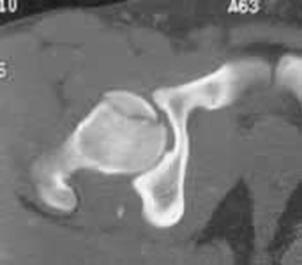

Luxatie de sold stang Luxatie de sold stang

Fractura

de cap femural Fractura de cap femural

Aspect

CT

de cap femural Fractura subcapitala cu usoara deplasare

Aspect CT